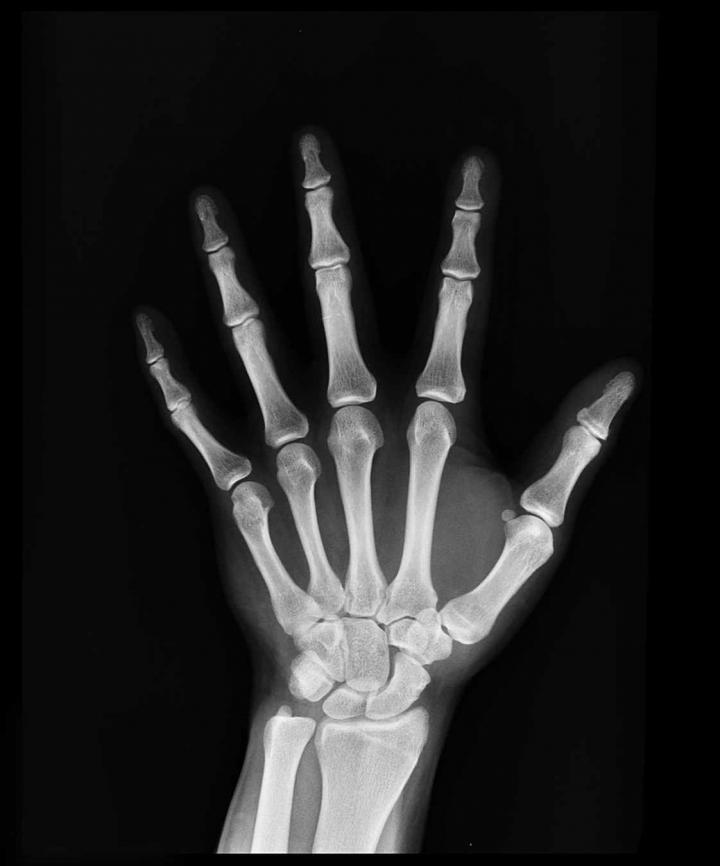

Hypophosphatasia in adults involves a loss of mineralization, which gives rise to recurrent fractures, femoral fractures, a history of rickets, and musculoskeletal pain, plus certain dental conditions. Among children it is much more serious, and can cause brain damage, respiratory problems, and even premature death in babies.